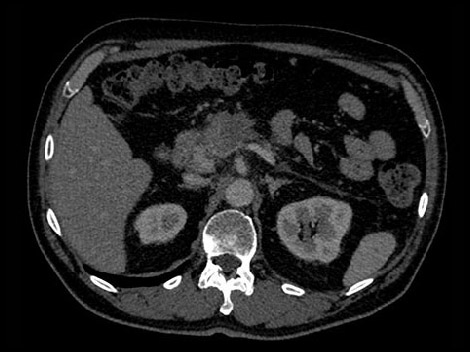

Возраст: 51 Рост: 1,82 м Вес: 79 кг КТ-ангиография брюшной полости при 70-секундной задержке введения контрастного вещества

В рассматриваемом гипотетическом случае рентгенологам требуется больше информации о подозрительном образовании в поджелудочной железе. Для постановки точного диагноза необходимо определить его материальный состав.